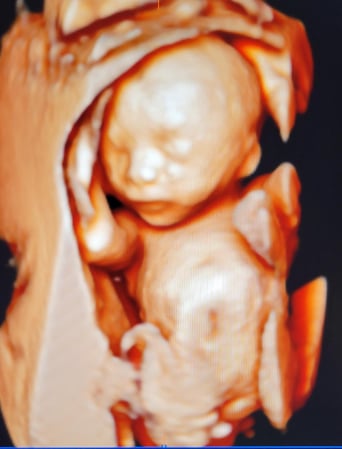

Tasha Crump, is registered by the American Registry of Diagnostic Medical Sonographers (ARDMS) and have over 18 years experience in medical diagnostic sonography specializing in Maternal Fetal Medicine. She is a highly proficient in the art of 3D 4D ultrasound. Tasha has practiced and trained in NYC's top ranked hospitals including Columbia Presbyterian. At Love at First Sight Imaging Studio you'll be in a very comfortable and calming atmosphere for you and your family to bond with your baby. We have state of the art equipment with HD Live to image unbelievably realistic views of your baby. You will fall in Love at First Sight.